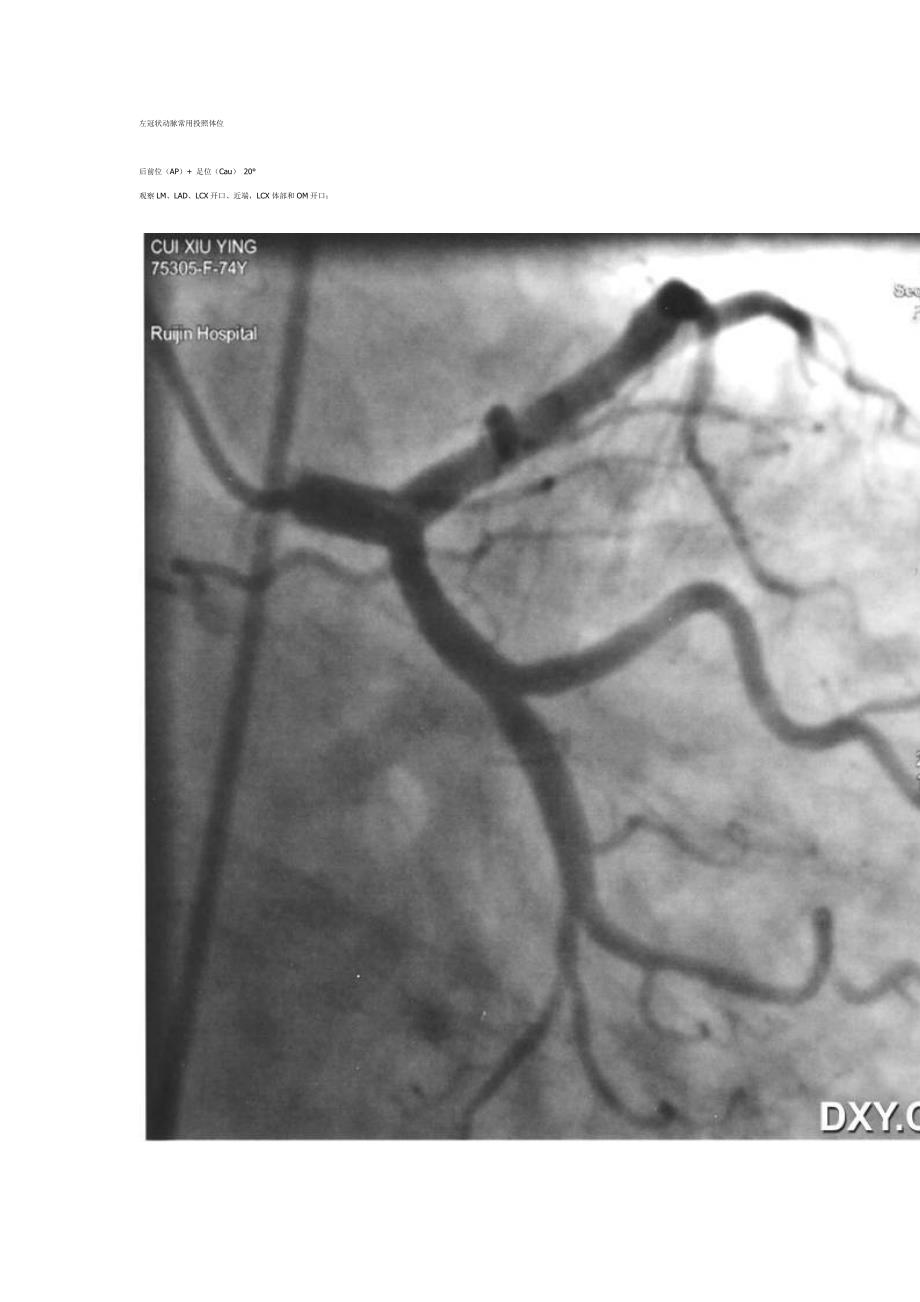

左冠状动脉常用投照体位后前位(AP)+ 足位(Cau) 20°观察 LM、LAD、LCX 开口、近端,LCX 体部和 OM 开口;左冠状动脉常用投照体位正位(AP)+头位(Cra)观察 LAD 近、中段,LAD 与对角支分叉处;观察 LM 开口用于支架定位左冠状动脉常用投照体位右前斜(RAO)30°+足位(Cau)20°(肝位):观察 LAD、LCX 起始部、LCX 全程、钝缘支(OM) 全程左冠状动脉常用投照体位右前斜(RAO)30°+头位(Cra)20°(右肩位)观察 LAD 中、远段左冠状动脉常用投照体位LAO 45°+ Cau 20°(脾位、蜘蛛位):观察 LM、LAD、LCX 开口病变(三分叉) ,LCX 体部、钝缘支(OM)开口和体部冠状动脉投照体位及 X 线解剖左前斜位 60°时,投照从心尖穿过,为心脏的正面观右前斜 30°时,投照垂直通过心脏的长轴,为心脏的侧面观左冠状动脉造影体位一览图右冠状动脉造影体位一览图右冠状动脉常用投照体位左前斜(LAO) 45° 右冠状动脉呈“C”型,观察 RCA 开口、起始部至后降支;The left anterior oblique view (LAO straight) shows the proximal and midportions of the right coronary artery (RCA) as well as the acute marginal branches (AM) and termination of the RCA in the posterior left ventricular branches (PLV). 机位图示意图解剖图右冠状动脉常用投照体位右前位(RAO)右冠状动脉象字母 “L”,观察 RCA 中段;The 30-degree right anterior oblique view (RAO) shows the midportion of the RCA, the conus branch, and the course of the PDA.机位图示意图解剖图右冠状动脉常用投照体位后前位(AP)+ 头位(Cra) 20?右冠状动脉呈“L”型,观察 RCA 远端分支及其开口情况;右冠状动脉常用投照体位左前斜位(LAO)+ 头位(Cra) 20°The 60-degree left anterior oblique view with 25 degrees of cranial angulation (LAO cranial) shows the midportion of the RCA and the origin and course of the posterior descending artery (PDA). 左冠状动脉造影基础体位:LAO 和 RAO实际操作时一般得加头或足,不过理解了这两个体位,再加头或足就好理解了。